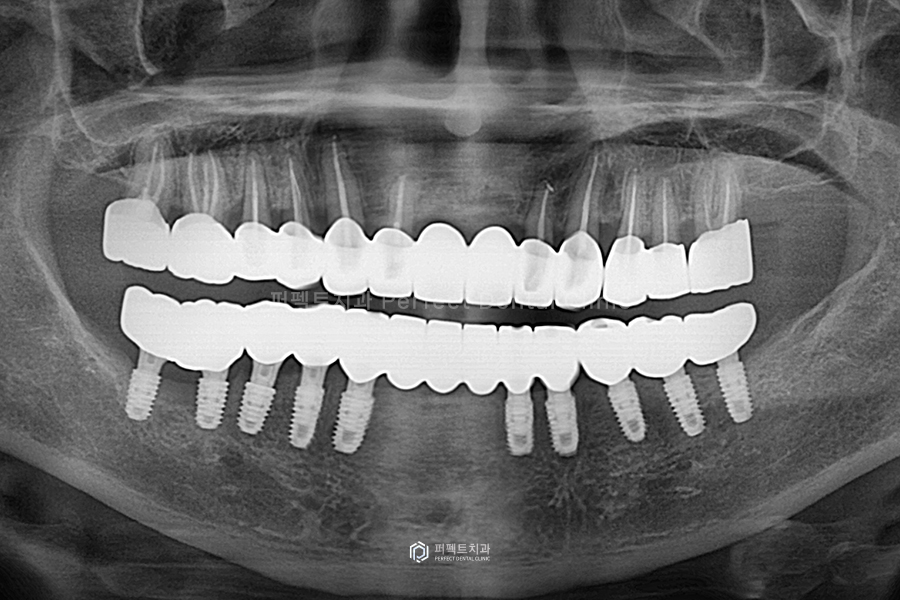

윗니까지 최종 치료를 마무리 한 사진입니다. 이렇게 하얗게 끝까지 잘 들어가 있는 것은 신경치료가 잘 됐다는 것을 의미합니다.

윗니 같은 경우에는 왼쪽 어금니 하나가 없는데 아래쪽에도 치아가 없어서, 즉 맞닿는 치아가 없어서 이렇게 마무리 하기로 하였습니다.

전후 사진을 보시면 교합평면 높이가 좋아지고, 전체적으로 치아가 반듯해진 것을 한 눈에 확인할 수 있습니다.

전체적으로 정리해서 말씀을 드리면 아랫니의 경우 흔들리는 앞니는 전부는 전부 발치하고, 임플란트를 10개 식립하였습니다. 윗니는 너무 흔들리는 앞니 두개만 발치를 했고, 나머지는 깨끗하게 신경치료를 한 후, 지르코니아 크라운으로 씌워서 사용하기로 하였는데요. 앞니는 걸어서 사용하는 브릿지로 완성하고 나머지는 싱글 크라운으로 하나씩 제작해서 사용할 수 있도록 해드렸습니다.